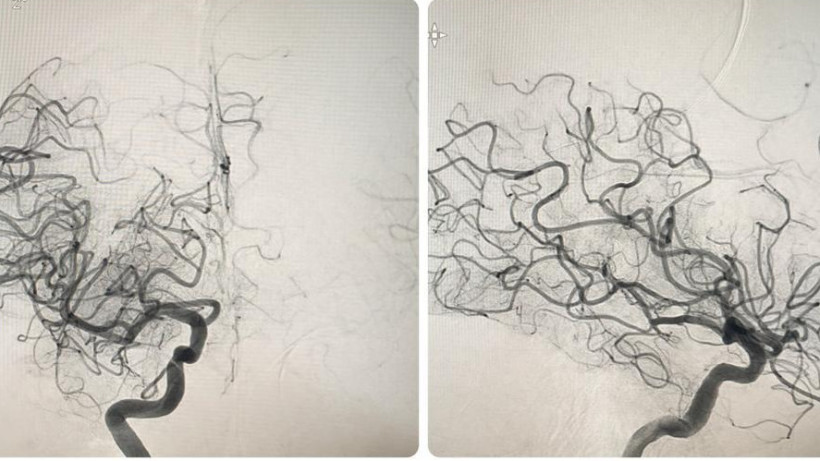

«Пациентка поступила с клинико-неврологической симптоматикой ишемического инсульта в бассейне правой средней мозговой артерии: левосторонний гемипарез, центральный парез лицевой мускулатуры слева, нарушение речи - дизартрия. Время начала заболевания 1 час. В экстренном порядке проведена операция - селективная церебральная ангиография, где выявлена картина острой окклюзии (тромбоз/тромбоэмболия) правой внутренней сонной артерии на уровне офтальмического сегмента», - делится информацией заведующий отделением сосудистой нейрохирургии Городской клинической больницы №7 Алматы Рауан Кастей.

Специалист подчеркнул, что образовавшийся тромб мог вызвать серьезные осложнения, вплоть до летального исхода. В ходе лечения была выполнена процедура рентгенэндоваскулярной механической тромбаспирации для извлечения тромба из правой внутренней сонной артерии. В этот раз использовался аспирационный катетер RED72, который недавно был внедрен в больнице, в замену ранее применяемому ACE62. По мнению нейрохирурга, новый катетер обладает рядом преимуществ, включая расширенный внутренний просвет для более эффективного удаления тромба, улучшенное гидрофильное покрытие для более плавного движения и глубокого проникновения, что в итоге способствует достижению наилучшего результата.

Внедрение этого нового оборудования значительно повысило качество оказания высокотехнологичной медицинской помощи в больнице. Операция была проведена успешно, без осложнений и рецидивов. Контрольная ангиограмма, выполненная после операции, подтвердила полное восстановление кровотока в бассейнах правой средней мозговой артерии и правой передней мозговой артерии.